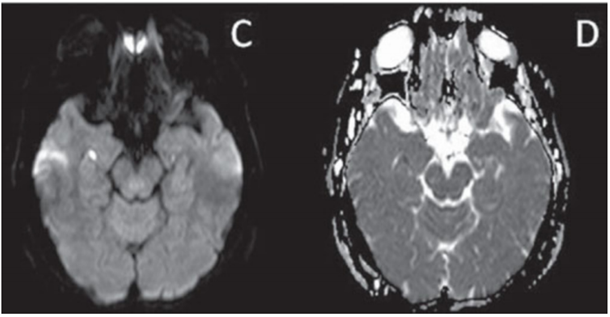

O padrão apontado pelas setas pretas na imagem de tomografia computadorizada (sem contraste venoso) abaixo é comumente observado em bronquiolite infamatória, inclusive infecciosa, como em casos de disseminação endobrônquica de micobacterioses.

Assinale a alternativa correta, que contém o padrão representado acima.